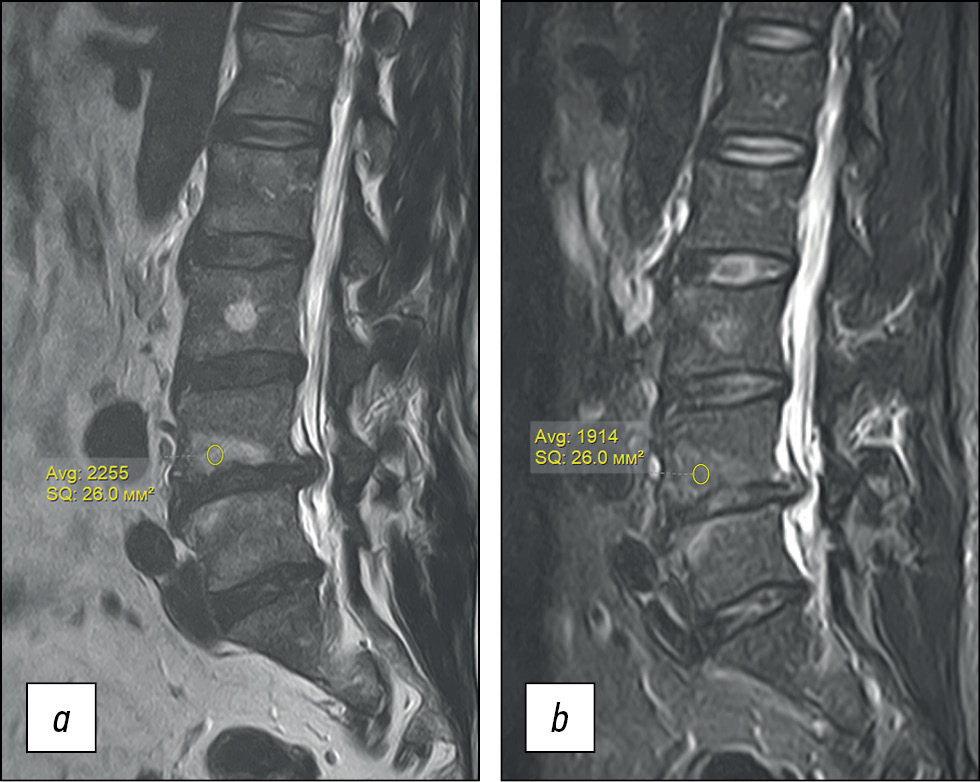

The image analysis operators used did not reveal significant differences in the differential signs of the presented edema and vertebral fat deposit cases. This is probably due to parallel processes, where areas of fatty degeneration with a reduced signal in STIR and uneven zones of subcortical osteosclerosis are determined against the subcortical peritrabecular edema (Fig. 4).

Fig. 4. MRI of the lumbar spine in the sagittal projection. T2WI, degenerative-dystrophic changes in a patient without an oncological history. a) Zones of heterogeneous subcortical edema are determined in the bodies of the vertebrae LIV, LV against the background of a herniated disc. b) In the STIR mode, the severity of edema appears to be reduced in relation to T2WI due to areas of fatty degeneration and subcortical sclerosis.